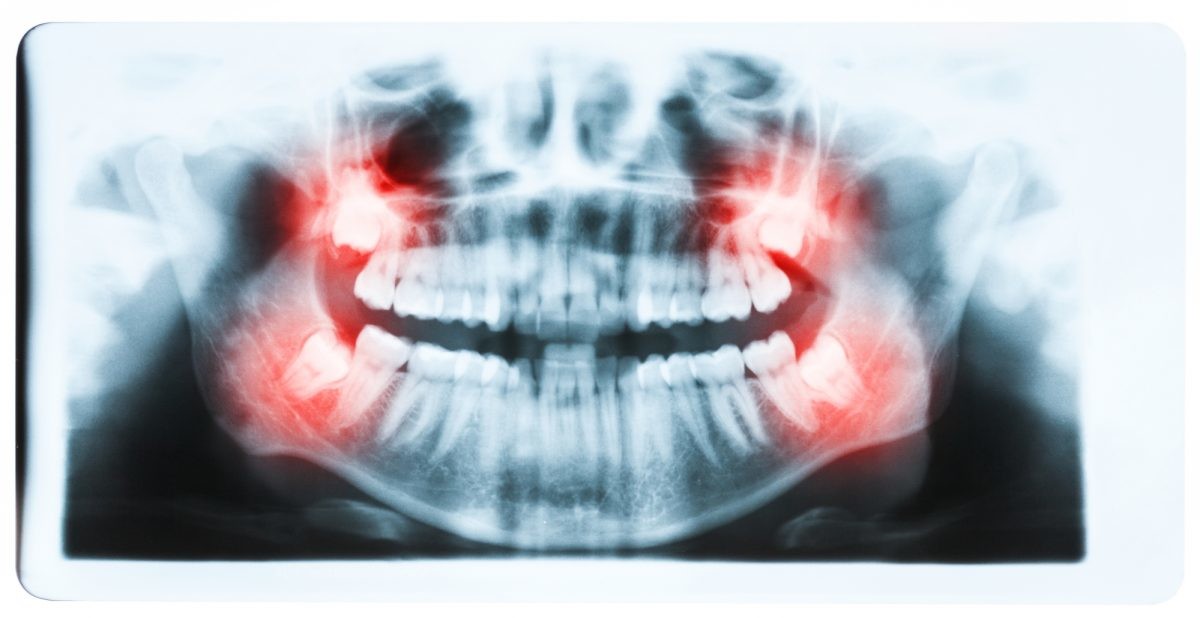

Do Wisdom teeth affect braces?

For those people who have wisdom teeth, they usually erupt in early adulthood. Wisdom teeth may cause dental issues like overcrowding, especially if they’re impacted. However, many people have plenty of room for their wisdom teeth and they have no problems with them.

Like previously stated, many people have their wisdom teeth come in with no problems. The teeth grow in straight and don’t affect the person’s bite. So overall, no, wisdom teeth do not cause significant overcrowding in the front of the mouth or severely disrupt any progress that was made with dental work like braces.

However, if they do not come in correctly or if a person’s jaw simply doesn’t have room for the new teeth, they can cause overcrowding among the back teeth.

While wisdom teeth may not necessarily cause a major issue with the dental progress that has been made with braces, there may still be reasons to have a wisdom tooth extraction. There are many wisdom tooth concerns that may call for tooth removal surgery, including: Crowding of back teeth, Infected gums, Bone defects, Root resorption, Dental diseases.

If a wisdom tooth becomes impacted or doesn’t erupt straight up, this can cause significant problems for the person. While some people may experience absolutely no problems with their wisdom teeth or get lucky enough to not have any of these extra molars at all, others may experience problems with them.

Fortunately, impacted tooth removal is a common procedure and can provide relief from any pain and discomfort caused by these teeth. In fact, wisdom teeth removal is more common than dental implant procedures, which about three million people have every year.

It’s important to remember that it’s perfectly normal for your teeth to move as you age. If your wisdom teeth are beginning to come in and are causing you pain and discomfort, your dentist may refer you to an experienced oral surgeon to discuss having them removed.